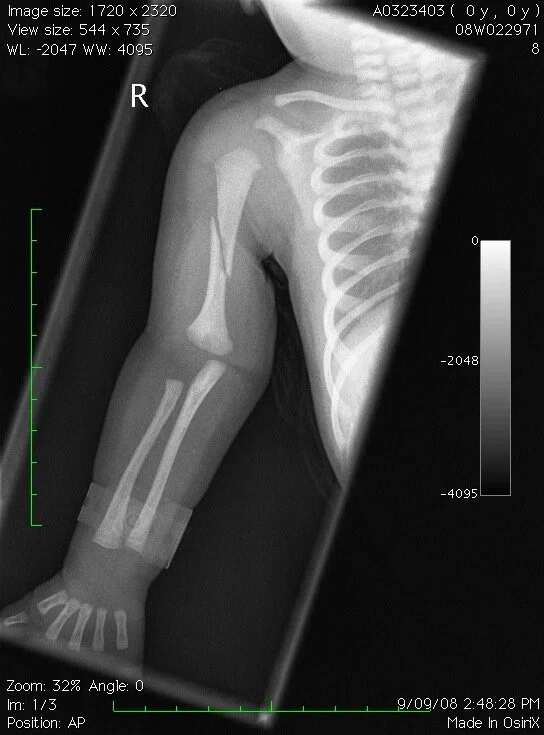

We've had a visit or two to the emergency department. Seems our third child takes the gong for most injury-prone. This image actually makes me want to cry - look at his chubby little newborn arms and that clear break in his bone!

My son's X-ray of his broken arm at 3 days old